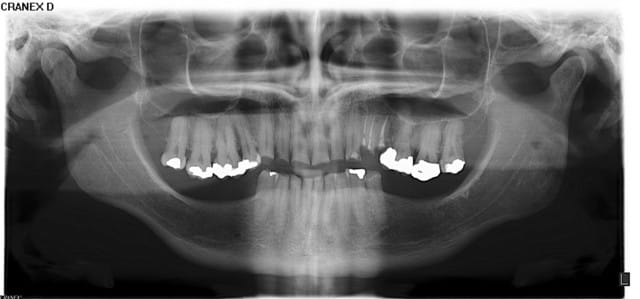

Pour PXAV et les autres

Pano yacadh - Eugenol

Pa jy0pvc - Eugenol

S2y2o1v7q53ws4r5wy6ou8czrpom - Eugenol

> Femme de 39 ans

> Histoire médicale RAS

> Pas de douleur (ATM, muscles, dents RAS)

> Demande solution globale/esthétique.

>

> La 21 mesure 8,6 mm par 3,6 mm de haut...

> hummm je crois qu'il y a usure...

> Alors des solutions ?

cas classique d'abrasion avec compensation au niveau des procès alvéolaires donc pas de perte de DV donc pas de surélévation

au niveau antérieur suivre ls principes de Peter Dawson

au niveau postérieur, coronoplasties , élongations coronaires pour recréer un plan occlusal correct,

après implants ou partiel